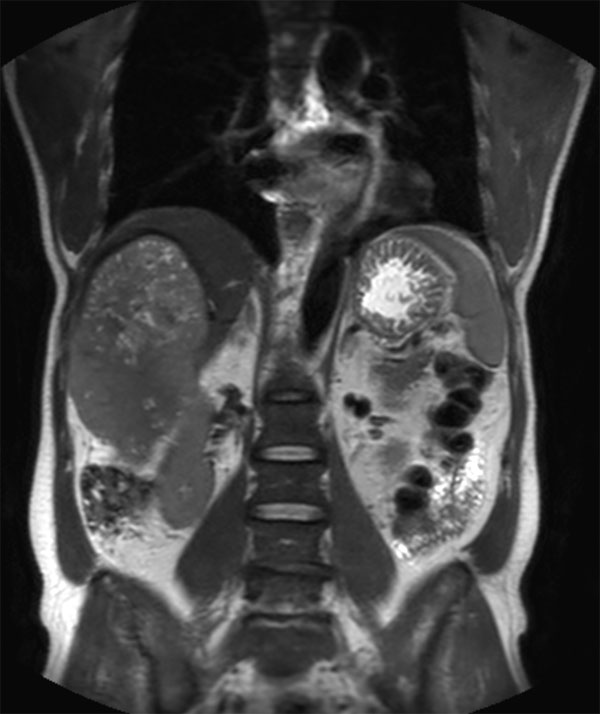

62 year old patient with huge, non-cirrhotic liver tumor. Question is if the portal vein is closed or not which has a direct influence on treatment options. Portal vein turned out to be open and patient was referred for embolization. No other tumors / lesions were found.

Coronal T2w TSE